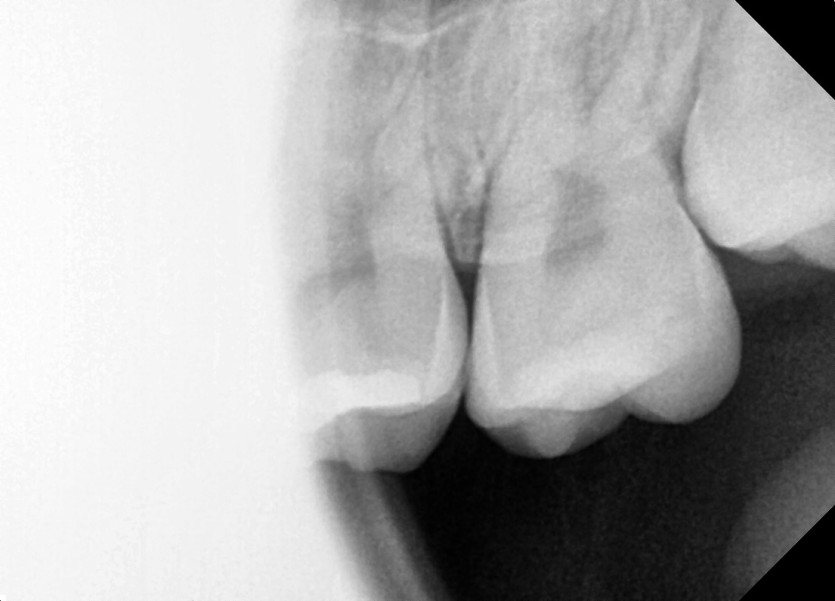

#28,38,48 사랑니 발치

구강 외과 전문의가 당일 발치했습니다.